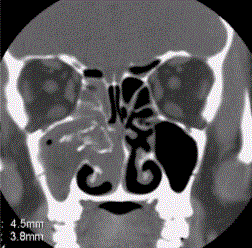

问题 患者男,35岁,鼻腔分泌物多,流脓涕,鼻塞,头痛,面部局部压痛1个月余。体检:鼻腔分泌物多,鼻黏膜肿胀。CT表现如下图。 真菌性鼻窦炎的并发症,表述正确的是

选项 A.可引起眼眶疏松结缔组织炎 B.可引起脑脓肿 C.可引起上颌骨骨髓炎 D.可加重扁桃体炎、咽炎、喉炎等 E.所致颅内并发症较眼眶并发症多见 F.病理可见真菌菌丝,曲菌、毛霉菌常见 G.CT显示窦腔膨胀性改变,内有弥漫分布的高密度影及散在高密度钙化

答案 ABCDFG